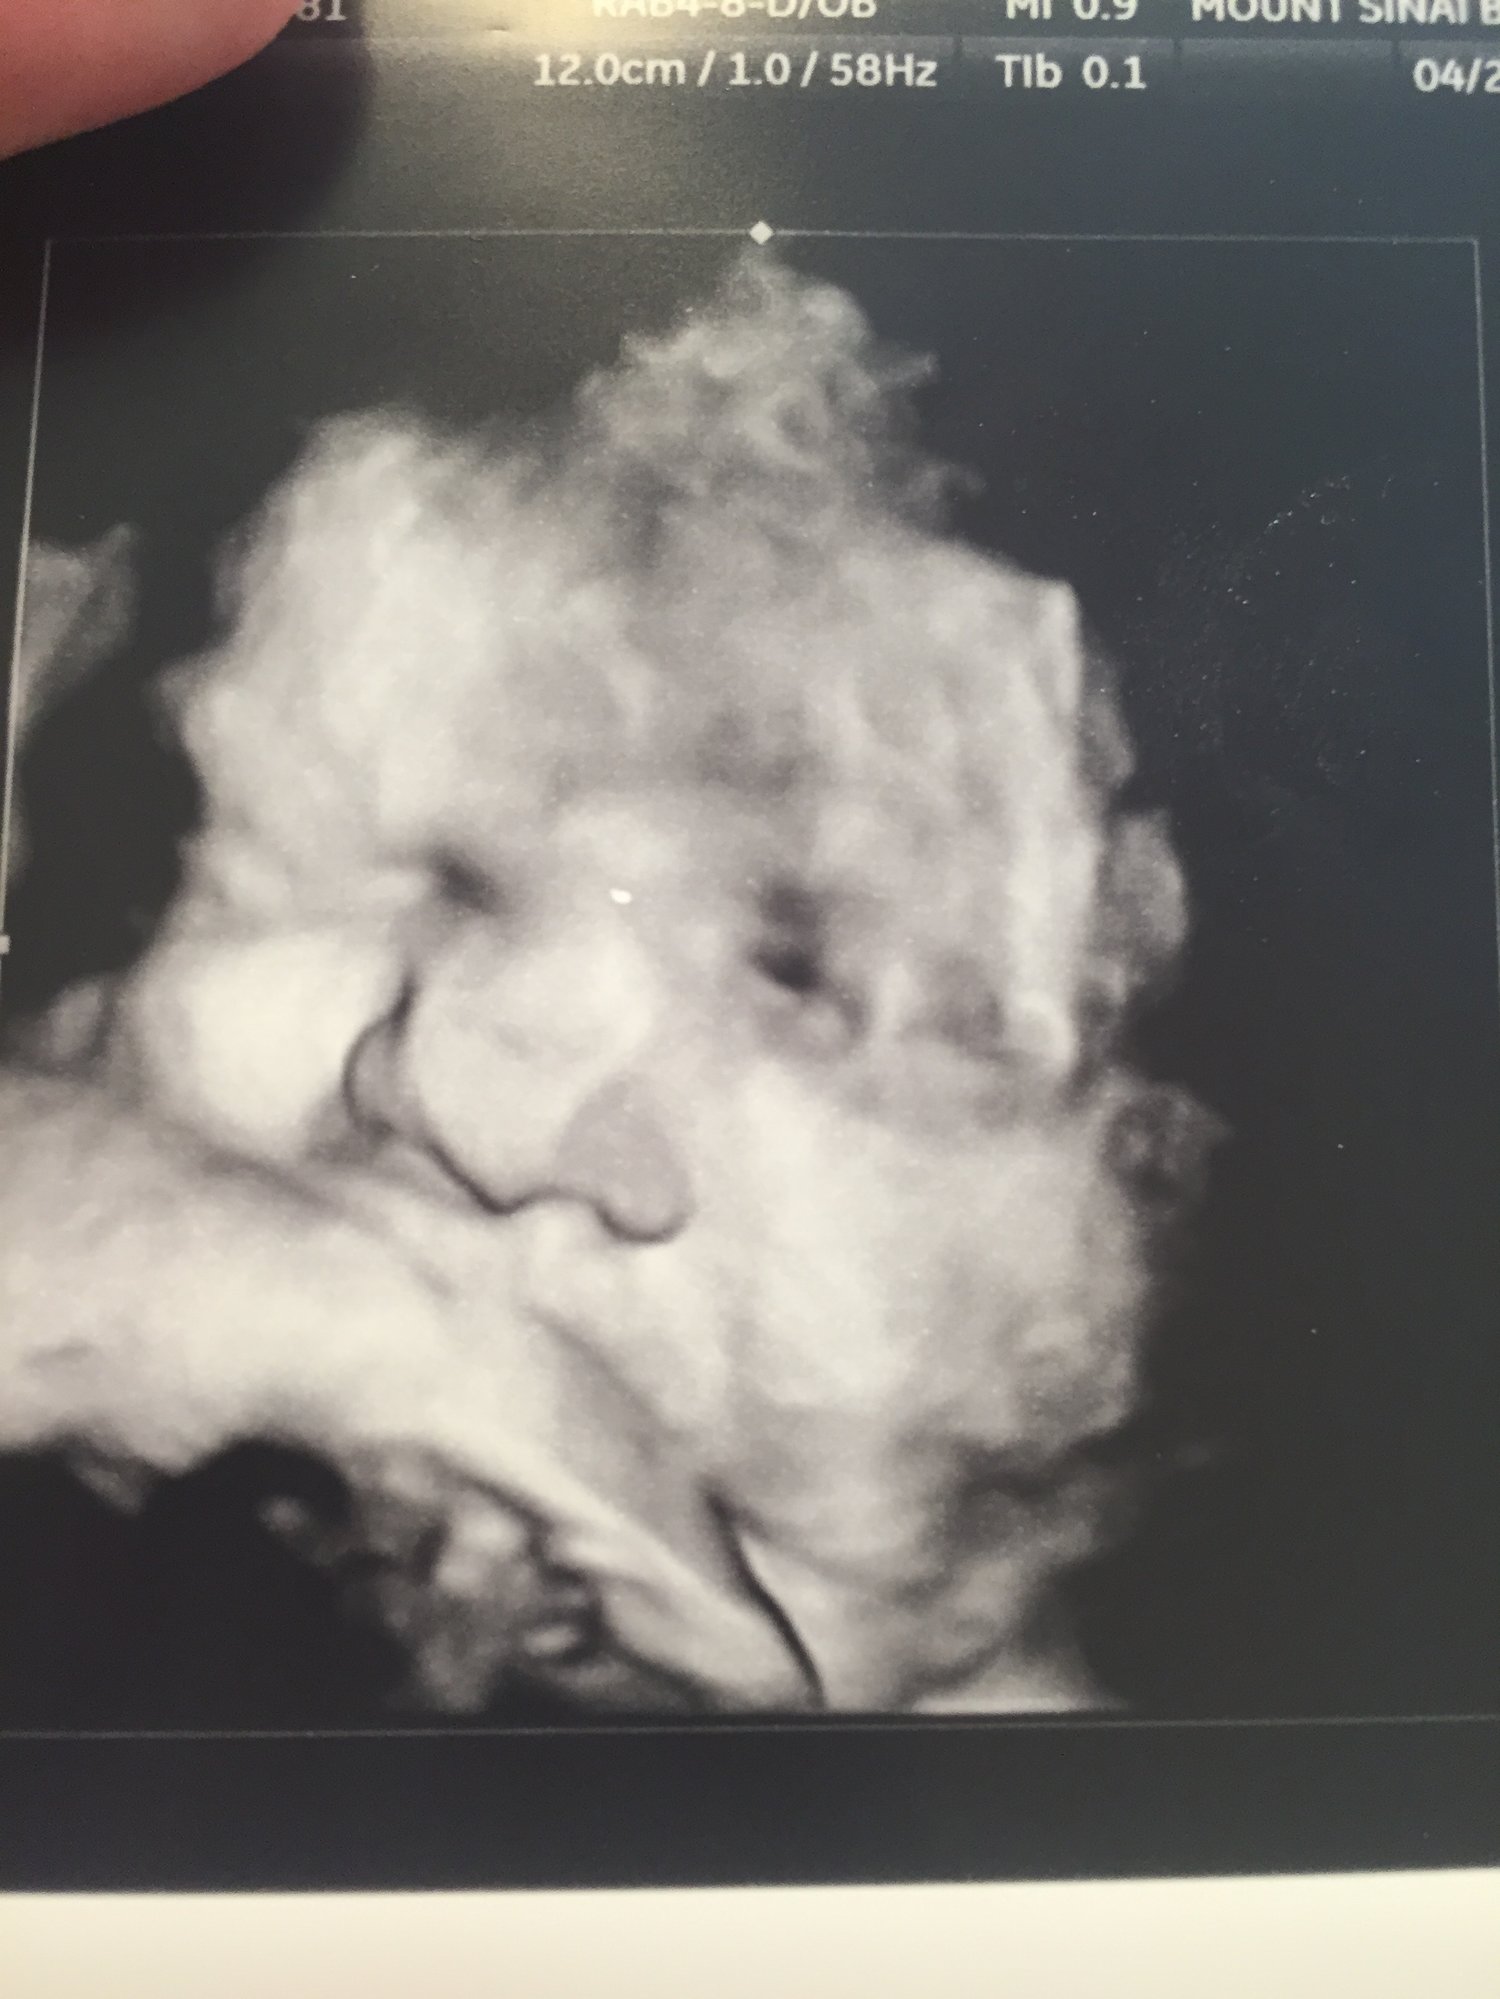

I had an appointment a couple of weeks ago with a MFM specialist to check out baby's kidneys because the right one was measuring larger than it should be. Thankfully, the kidney checked out all right, but they noticed that one of the ventricle walls on his heart is thicker than it should be. The doctor said this was no cause for alarm, but he normally sees this on women that have gestational diabetes (and I do not) and wants to follow up. He wanted me to come back on 4 weeks so they could get another look at the heart. I made the next appointment for the late afternoon, hoping that DH (teacher) could come. Well, he says he has spring football practice that week, and it would be hard for him to miss. So, I asked if he could come if I changed it to a morning appointment, and he just kind of brushed me off, saying that it's state test week, and he really didn't need to miss class.